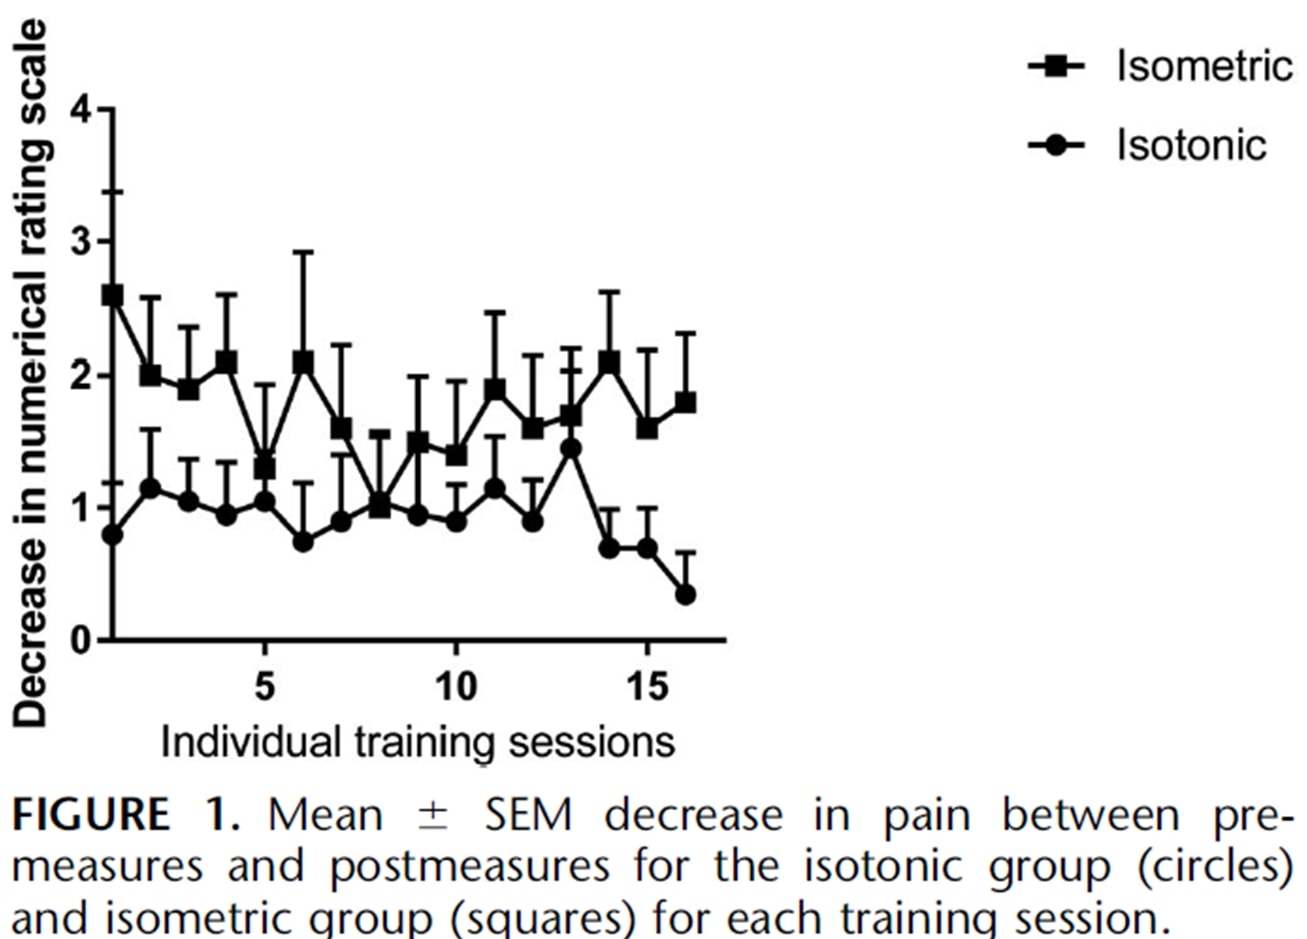

同一作者还在两年后对跳跃运动员进行了赛季内跟踪研究(Rio et al. 2017)中,他们对等长程序和等张程序进行了比较。 在这项研究中,两组的结果差异较大,等长组的即时疼痛减轻程度更高:

最近的一项研究 霍尔登等人 (2019)也研究了等长运动对髌骨肌腱病的影响,但没有发现任何镇痛效果:

图自 Holden 等人 (2019)

然而,髌骨肌腱病通常是年轻跳动男性的疾病,女性比例高和平均年龄相对较高的情况并不典型。 因此,在某些病例中,髌腱病的诊断可能并不正确。 虽然这两项研究是针对髌骨肌腱病进行的,但让我们看看能否将这些结果应用到其他肌腱上。